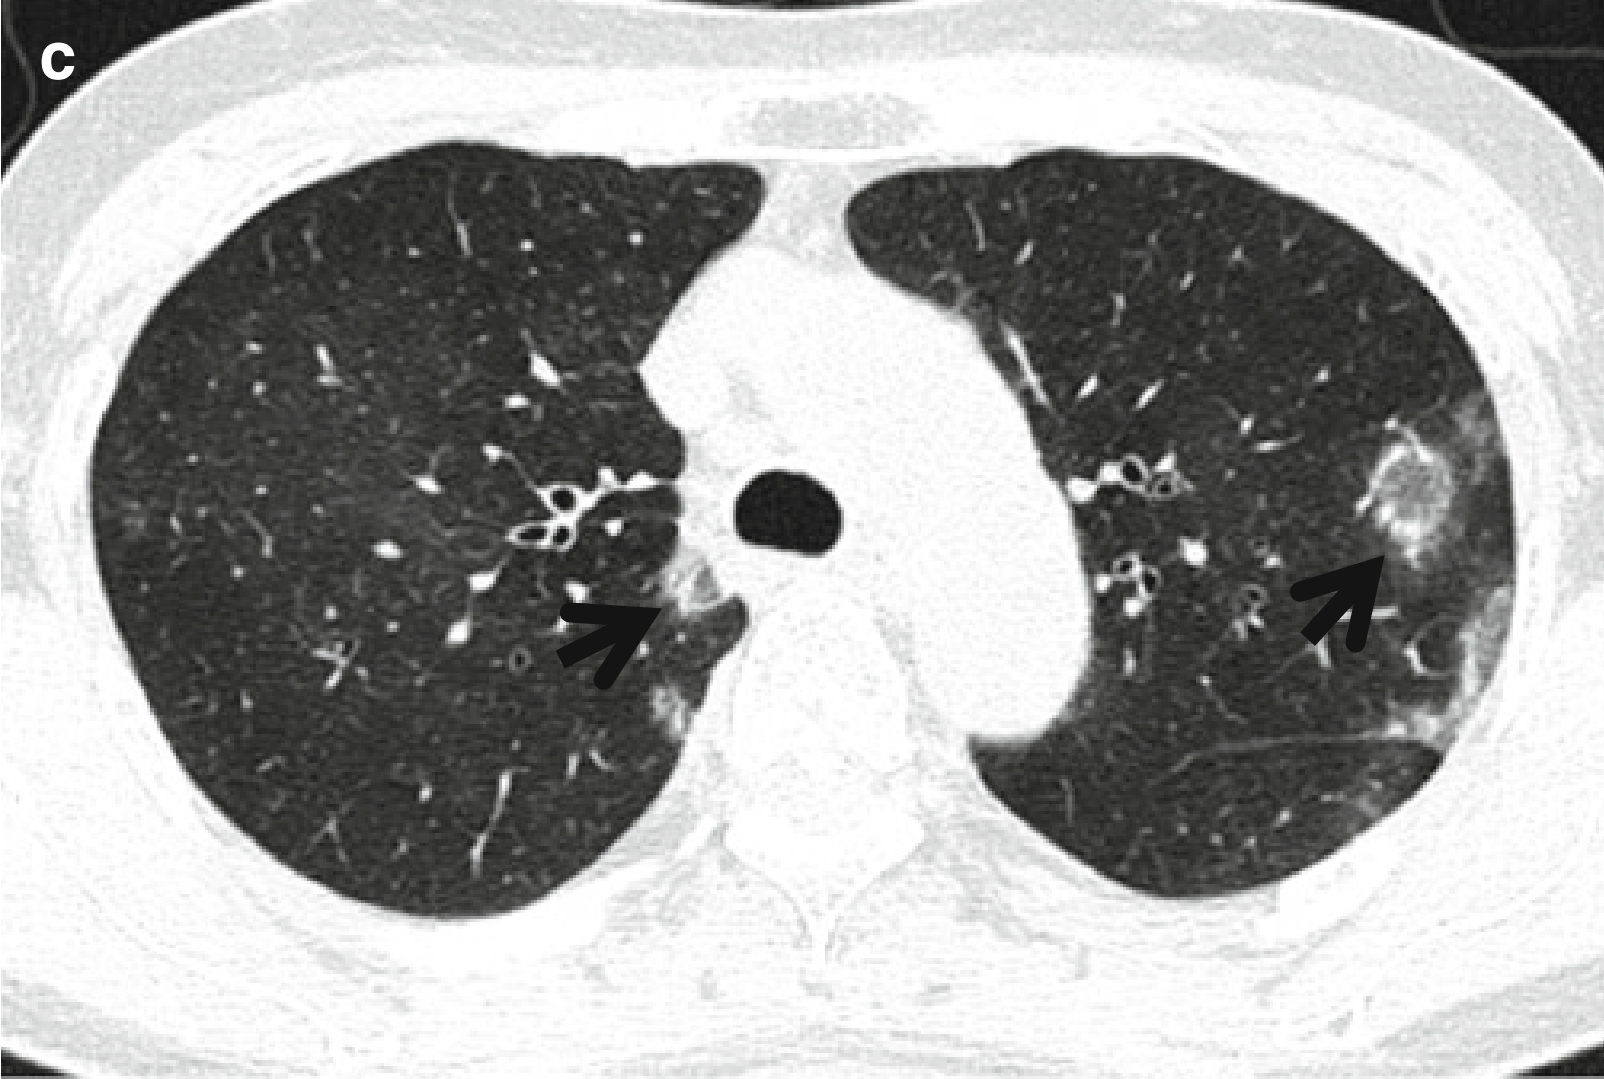

图8.4 男,70岁,淋巴瘤样肉芽肿病患者、可见反晕征。

CT扫描(层厚=5.0mm)肺窗于左肺下叶支气管水平可见双肺多发大小不等的结节,双侧肺门淋巴结肿大。部分结节可见反晕征(箭头所示)。

CT表现:典型CT表现为多发肺结节和肿块,病灶中央为低密度,外围呈环形强化,可见磨玻璃密度晕征或反晕征(图8.4)。结节和肿块主要见于双肺下叶,并沿支气管血管束和(或)胸膜下分布,也可见粗糙不规则密度增高影和薄壁小囊肿。